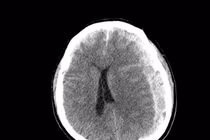

Hình ảnh tổn thương xương sọ trên phim chụp - Ảnh BVCC

Kết quả thăm khám và chẩn đoán hình ảnh cho thấy gãy xương sọ phức tạp nhiều mảnh di lệch, kèm xuất huyết nội sọ, dập não khu trú vùng trán, phù não và nguy cơ tổn thương màng cứng, nhu mô não.

Đây là tổn thương đặc biệt nguy hiểm ở trẻ nhỏ, có thể nhanh chóng dẫn đến tăng áp lực nội sọ, phù não tiến triển, rối loạn ý thức và để lại di chứng thần kinh nặng nề nếu không được phẫu thuật kịp thời.